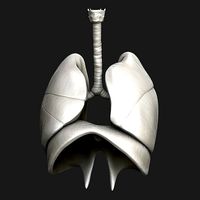

Lungs MAX 2008 3D Model

...3d model 3dexport respiratory anatomy lung trachea larynx thyroid thorax bronchiole bronchus lungs max 2008 3d model motionmediaworkshop 70618...

Lungs MAX 2008

...max 2008 3docean anatomy bronchiole bronchus larynx lung respiratory thorax thyroid trachea lungs max 2008 ========content========= lungs polygons: 321...